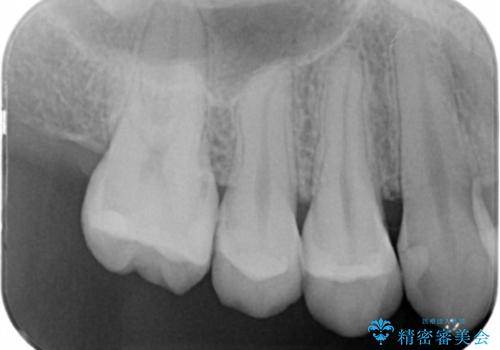

変色した詰め物の再治療 セラミックインレー

- 以前保険で治療した詰め物の変色を治したいとの主訴でご来院されました。

審美性と耐久性に優れたセラミックインレーで治療しました。

セラミックは素材の色調が歯に近く経年的な変色もないため、長期の審美性維持が可能となります。

歯の一部が虫歯になってしまった場合の治療法のひとつにインレーがあります。

虫歯になってしまった部分を含めて詰め物用に形を削り整え、型取りをし、出来上がってきた技工物をセメントで接着します。

自費治療では強度・色調・耐久性に優れたセラミックを使用した治療を選択する方が多いです。